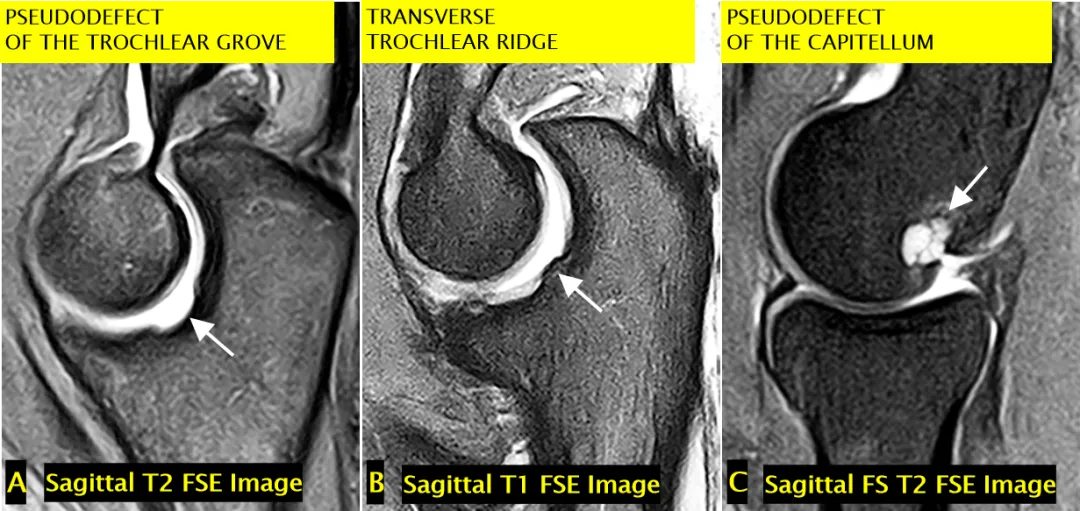

正常变异与诊断陷阱(一)

• 滑车沟假缺损(A 图):不应与骨软骨缺损混淆(箭头标注);成像序列:矢状面 T2 加权快速自旋回波图像;

• 横行滑车嵴(B 图):不应与中央骨赘混淆(箭头标注);成像序列:矢状面 T1 加权快速自旋回波图像;

• 肱骨小头假缺损(C 图):肱骨小头后下侧的正常裸露区(箭头标注),不应与骨软骨损伤混淆;成像序列:矢状面脂肪抑制 T2 加权快速自旋回波图像;

• 3 幅对应 MRI 图像(标注 A-C)